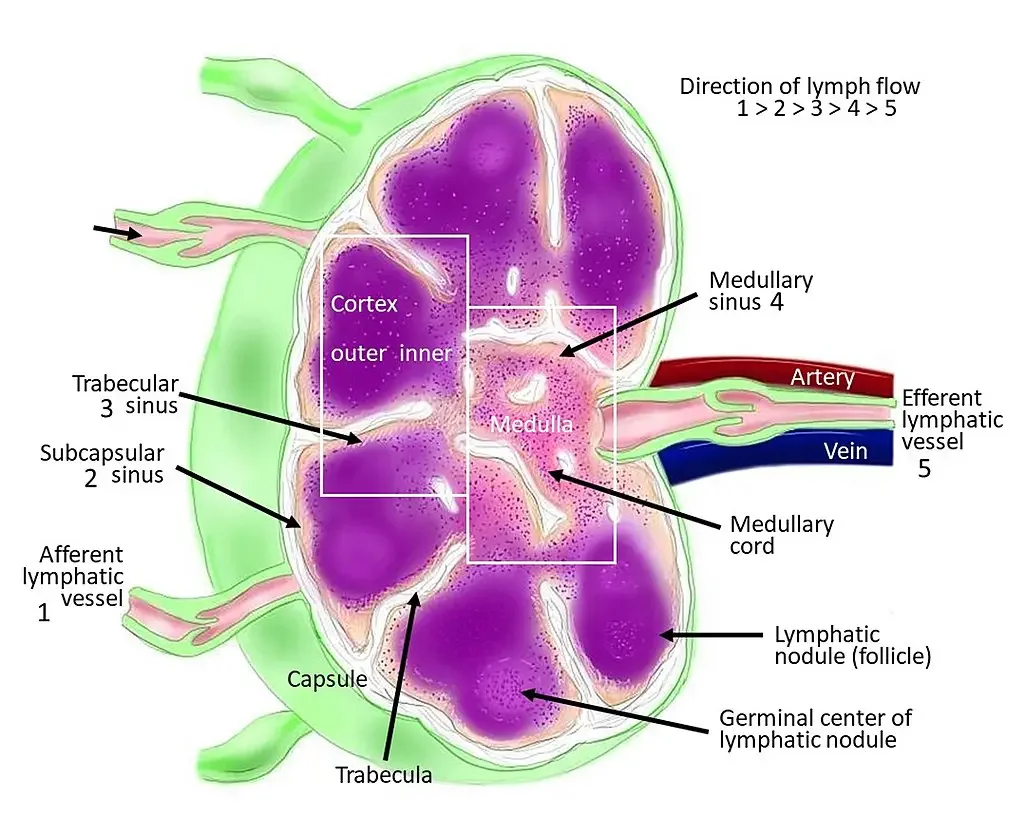

Изображения и схемы: как выглядит лимфа